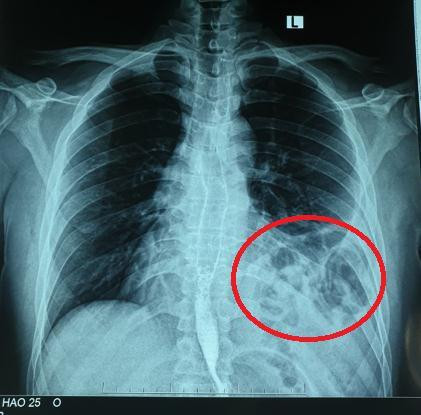

![]() |

| Bóng khí của đại tràng ở trên ngực trái trên X - quang. Ảnh: BS cung cấp |

Bệnh nhân Đ.A.H, nam 25 tuổi với tiền sử khỏe mạnh. Hơn một năm trước, bệnh nhân bị tai nạn giao thông xe máy tự ngã, bị đập ngực trái xuống đường. Sau tai nạn, H. thấy đau tức ngực nhẹ, không khó thở nên không đi khám. Trong thời gian tiếp theo, H. thấy cơ thể bình thường khi sinh hoạt lao động nhẹ, chỉ xuất hiện khó thở khi khuân vác các vật nặng. Điều này chưa khiến H. cảm thấy bất thường trong cơ thể mà chỉ nghĩ đơn giản là do làm việc quá sức. Khoảng 5 tháng trước, H. bị mắc COVID-19 tự điều trị tại nhà. Tuy nhiên, sau khi khỏi bệnh, các triệu chứng ho và đau tức ngực vẫn tồn tại và có dấu hiệu nặng lên. Nghĩ mình bị hậu COVID nên H. vẫn tự điều trị tại nhà. Tuy nhiên, một tháng trở lại đây, H. thấy đau tức ngực kèm ho và khó thở tăng lên. Nghĩ rằng mình đang có vấn đề về đường hô hấp sau khi mắc COVID-19 nên H. đã đi khám chuyên khoa hô hấp tại Bệnh viện Bạch Mai. Tại đây, H. đã được chỉ định chụp X.quang ngực và được phát hiện có tình trạng có hình bóng hơi của ruột ở trên ngực trái.

- Chụp X.quang: Dấu hiệu mất liên tục vòm hoành, có hình ảnh mức nước hơi của quai ruột trong lồng ngực.